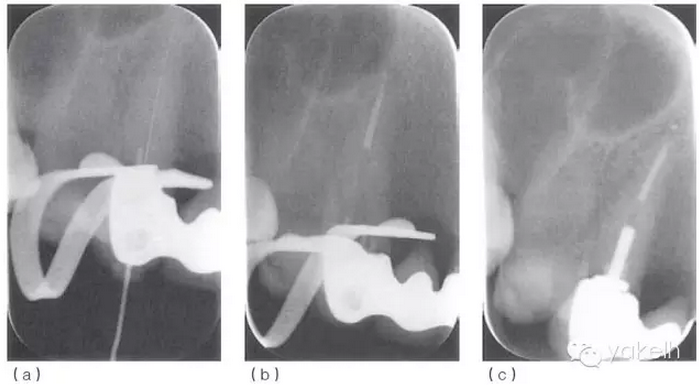

¤¤使用根尖定位儀確定根管的工作長度,拍攝X線片(圖 5.2.2a)加以驗證。采用化學-機械方法進行完善的根管預備后,使用牙膠和根管封閉劑,采用熱垂直加壓技術(shù)進行根管充填(圖5.2.2b,c)。1個月后復診,患者無癥狀,潰瘍變小,僅黏膜表面遺留瘢痕(圖 5.2.3)。

圖 5.2.2(a)13確定工作長度的X線片。(b)13根管充填中X線片。(c)13根管充填后X線片。